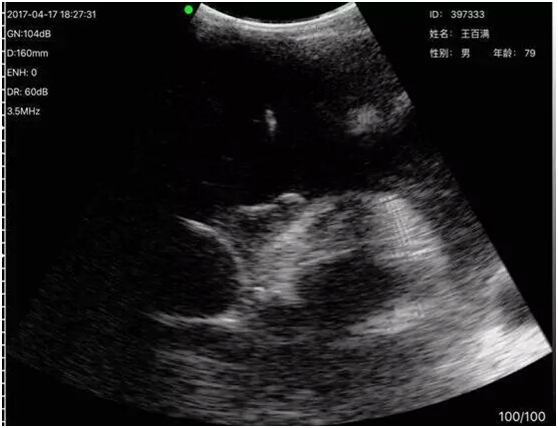

术中超声动态引导图像效果

王大爷患“慢性阻塞性肺病” 30余年,2个月前受凉后病情加重,在当地医院治疗效果不佳,听人介绍辗转至咸阳市第一人民医院呼吸内科二病区就诊,来时已是下班时间,值班医生梁杰接诊后,发现患者精神极差,胸闷、气短症状明显,胸部CT检查发现患者心包大量积液。梁医生意识到情况不妙,立即向科室主任亢锴汇报。亢主任赶到科室,现场应用无线探头式超声为患者进行了快速探查,当即明确存在大量心包积液,并确定了较为理想的穿刺部位。在与患者及家属细致沟通后,亢锴主任及梁杰医生在床旁为患者实施了本市首例无线探头式超声实时引导下心包积液穿刺闭式引流术。术中,亢锴主任手持超声、眼盯IPAD屏幕,再次对穿刺部位、穿刺方向、穿刺角度及深度进行了确定,同时指导梁杰医生在超声实时引导下实施穿刺引流术,一根细细的软管将积聚在王大爷心包腔内的液体缓缓引出,王大爷胸闷症状逐渐缓解,紧锁的眉头开始舒展,手术顺利结束!在病房外焦急等待的家属进门后看到王大爷神态自若,与治疗前后判若两人,几乎不敢相信自已的眼睛,再三询问老人感觉如何,当得到老人肯定的回答时,家属们激动地对两位医生竖起了大拇指,连声称赞医生医术高明、设备先进!